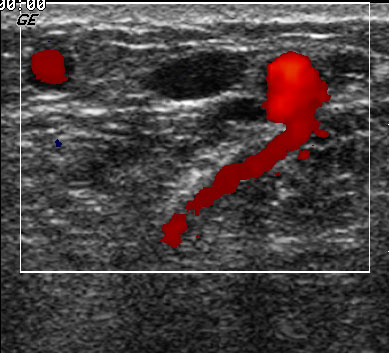

Insufficiënte vena perforans

therapiePerforerende venen kunnen gescleroseerd worden. Vaak is

er aan de buitenkant een blow-out zichtbaar. Dit is precies de plek waar ingespoten

moet worden. Voor een goed resultaat is meestal een hoge concentratie nodig

(3%) en een volume dat voldoende is om de blow out goed te vullen (0.5-1 ml).

Het is ook mogelijk om rechtstreeks in de perforans in te spuiten in plaats

van in het overliggend vat of in de blow-out. Dit is echter niet zonder risico.

Bij teveel inspuiten kan scleroseringsvloeistof in het diepe systeem terechtkomen

met risico op diepe veneuze trombose. Daarnaast lopen vlak naast de venae perforantes

ook arterietakken die per abuis kunnen worden geraakt.